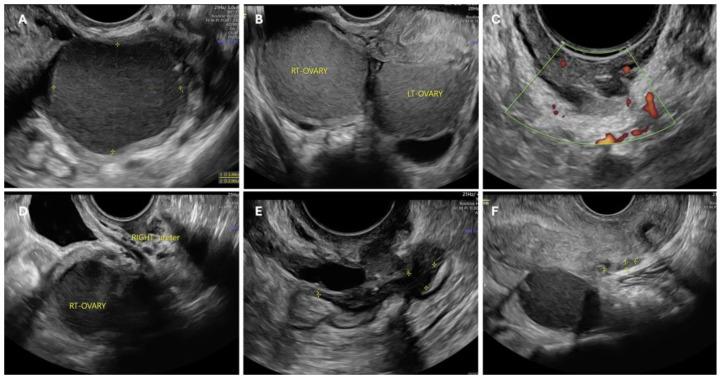

Endometriosis is a chronic, estrogen-dependent inflammatory disease characterized by the presence of endometrial tissue outside the uterus, causing pelvic pain and infertility. Infertility arises mainly due to inflammatory mediators in the peritoneal fluid, contributing to local hypoestrogenism, which appears to exacerbate chronic inflammation and sensitize pelvic nerves. Local hypoestrogenism within endometriotic lesions contrasts with the systemic estrogen-dependent nature of the disease. This localized reduction in estrogen levels, resulting from an altered hormonal response, can contribute to the altered immune response and inflammation characteristic of endometriosis, potentially exacerbating tissue damage, promoting fibrosis, adhesions, and endometrioma formation that distort pelvic anatomy, and affecting fertility. Chronic pelvic pain and dyspareunia further complicate conception in affected women. In vitro fertilization (IVF) and laparoscopic surgical excision of endometriotic lesions are the two primary management options for endometriosis-related infertility, although current data provide limited guidance on when to prefer one approach over the other. It is generally accepted that treatment strategies must be individualized according to the patient's wishes, symptomatology, age and the preferences of the woman and the couple. Timely intervention and structured follow-up for symptomatic women wishing to conceive may maximize conception rates within two years post-surgery, while minimizing the need for repeated interventions, which should be avoided. On the other hand, first-line IVF is particularly viable in cases of unoperated deep infiltrating endometriosis in asymptomatic women, or for those ineligible for or opposed to surgery. This review aims to evaluate the most recent data on endometriosis-related infertility to identify evidence-based key points that can enhance tailored management in clinical practice.

子宫内膜异位症是一种慢性、雌激素依赖性炎症性疾病,其特征是子宫外存在子宫内膜组织,可导致盆腔疼痛和不孕。不孕主要是由于腹腔液中的炎症介质所致,这些介质会导致局部雌激素水平降低,这似乎会加剧慢性炎症并使盆腔神经敏感化。子宫内膜异位症病灶内的局部雌激素水平降低与该疾病的全身性雌激素依赖性本质形成对比。这种因激素反应改变导致的雌激素水平局部降低,可能会导致子宫内膜异位症特有的免疫反应和炎症改变,从而可能加剧组织损伤、促进纤维化、粘连和子宫内膜瘤形成,进而扭曲盆腔解剖结构并影响生育能力。慢性盆腔疼痛和性交困难会使受影响女性的受孕更加复杂。体外受精(IVF)和腹腔镜手术切除子宫内膜异位症病灶是治疗子宫内膜异位症相关不孕的两种主要方法,尽管目前的数据对于何时优先选择一种方法而非另一种方法提供的指导有限。人们普遍认为,治疗策略必须根据患者的意愿、症状、年龄以及女性和夫妇双方的偏好进行个体化制定。对于希望受孕的有症状女性,及时干预和结构化随访可在术后两年内使受孕率最大化,同时尽量减少重复干预的必要性,应避免重复干预。另一方面,一线IVF在无症状女性未手术的深部浸润性子宫内膜异位症病例中,或对于那些不适合手术或反对手术的女性中尤其可行。本综述旨在评估关于子宫内膜异位症相关不孕的最新数据,以确定可在临床实践中加强个体化管理的循证关键点。